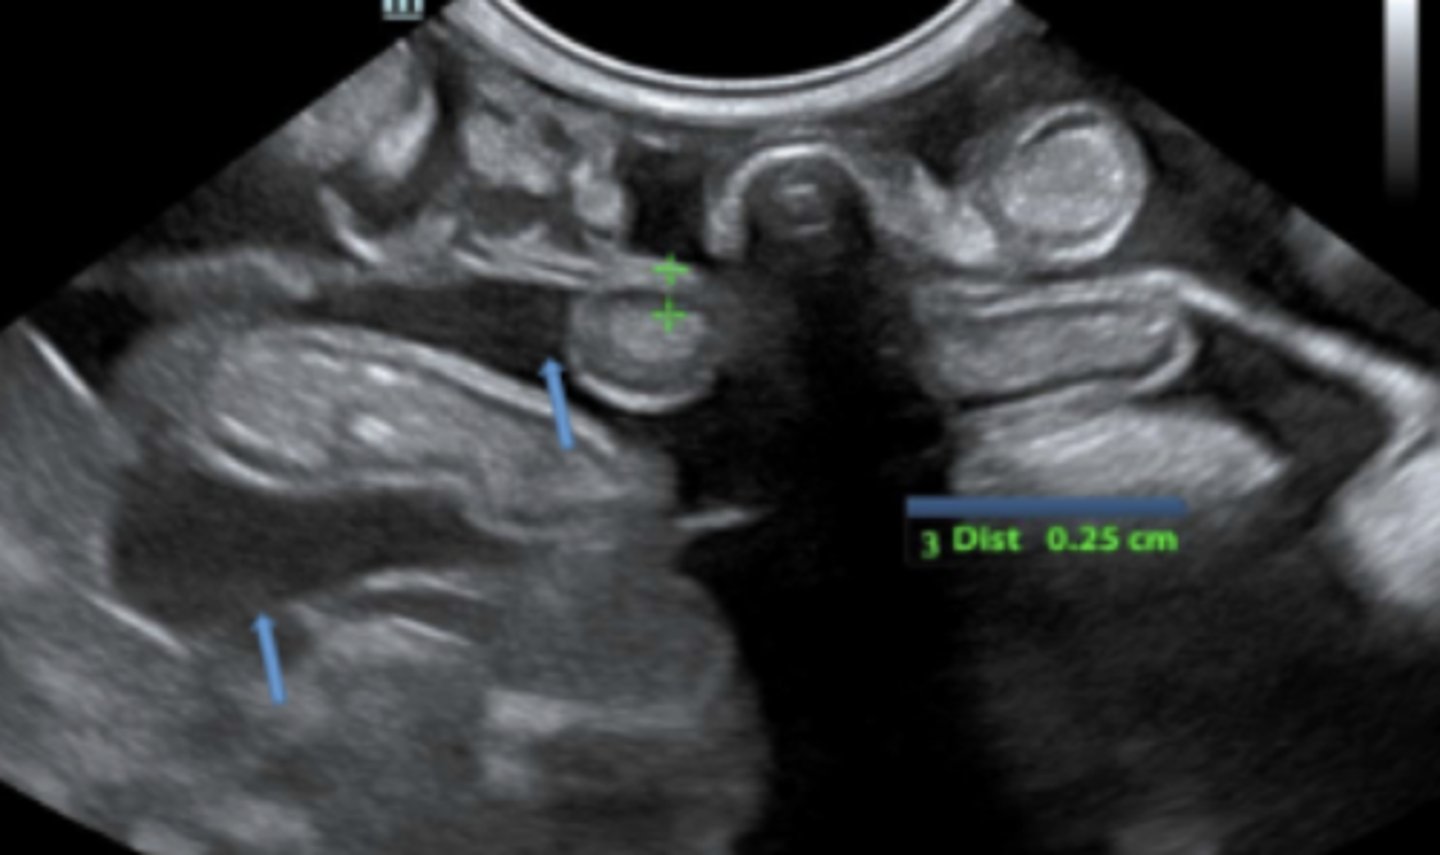

(objeto hiperecoica + sombra)

patología:

cuerpo extraño en estomago